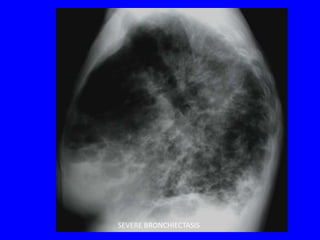

SEVERE BRONCHIECTASIS